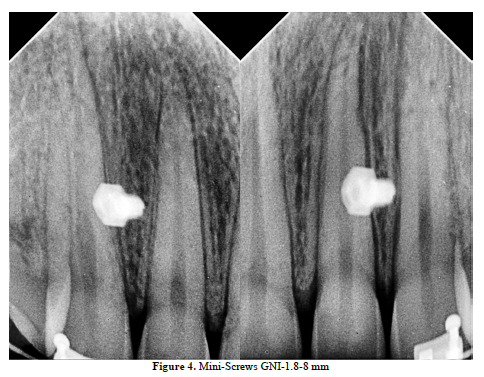

The solution of TADs has improved the aesthetic appearance, the patient’s smile and even the patient’s Cupid’s bow “Smile Arc”, Figure 4, 5.

Hitherto, the cephalometric and clinical outcomes support the aforementioned approach (Figure 6).